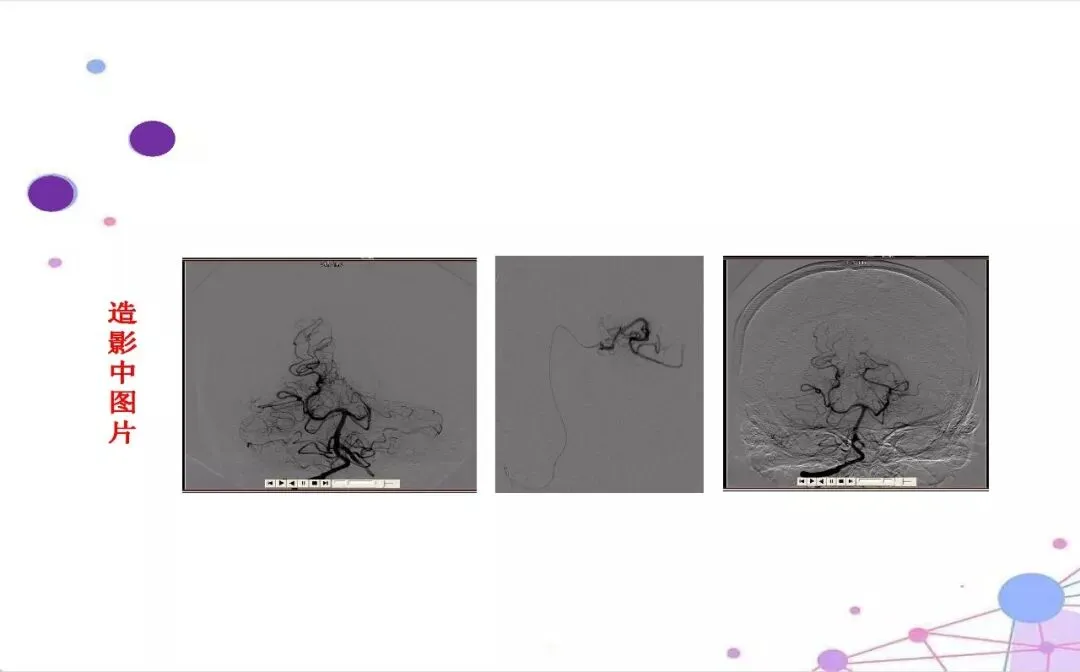

【介入PPT·可下载】大面积脑梗介入手术围术期的护理